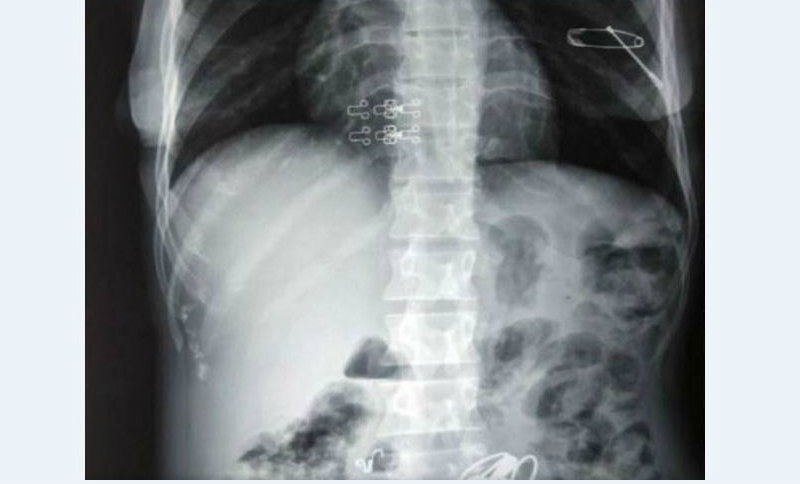

ಕೆಲವು ದಿನಗಳಿಂದ ಸಂಗೀತ ಹೊಟ್ಟೆ ನೋವಿನಿಂದ ನರಳುತ್ತಿದ್ದಳು. ಇದನ್ನು ಕಂಡ ವೈದ್ಯರು ಆಕೆಯನ್ನು ಸ್ಕ್ಯಾನಿಂಗ್ ಗೆ ಒಳಪಡಿಸಿದಾಗ, ಹೊಟ್ಟೆಯಲ್ಲಿ ಕಬ್ಬಿಣದ ಮೊಳೆಗಳು, ಪಿನ್ಗಳು, ಯು-ಪಿನ್ಗಳು, ಬಳೆ-ಸರ, ಮಂಗಳಸೂತ್ರ ಸೇರಿದಂತೆ ಹಲವು ಕಬ್ಬಿಣದ ವಸ್ತುಗಳು ಇರುವುದು ಪತ್ತೆಯಾಗಿತ್ತು. ಅದರಲ್ಲೂ ಒಂದು ಪಿನ್ ಸಂಗೀತಾಳ ಕರಳಿಗೆ ಚುಚ್ಚಿಕೊಂಡಿದ್ದ ಕಾರಣ ತಕ್ಷಣ ಆಕೆಗೆ ಶಸ್ತ್ರಚಿಕಿತ್ಸೆ ಮಾಡಿ, ಹೊಟ್ಟೆಯಲ್ಲಿದ್ದ ಸರಿಸುಮಾರು 1.5 ಕೆ.ಜಿ ತೂಕದ ಕಬ್ಬಿಣದ ವಸ್ತುಗಳನ್ನು ಹೊರ ತೆಗೆಯಲಾಯಿತು ಎಂದು ನಾಗರಿಕ ಆಸ್ಪತ್ರೆಯ ಶಸ್ತ್ರಚಿಕಿತ್ಸೆ ವಿಭಾಗದ ಹಿರಿಯ ವೈದ್ಯರಾದ ಡಾ. ನಿತಿನ್ ಪಾಮರ್ ತಿಳಿಸಿದರು.

ಮಾನಸಿಕ ಅಸ್ವಸ್ಥ ರೋಗಿಗಳಲ್ಲಿ ಅಕ್ಯುಫಾಗಿಯಾ ಎಂಬ ರೋಗ ಲಕ್ಷಣವಿರುವವರು ಕಬ್ಬಿಣದ ವಸ್ತುಗಳು ಹಾಗೂ ಚೂಪಾದ ಯಾವುದೇ ವಸ್ತುಗಳನ್ನು ತಿಂದುಬಿಡುತ್ತಾರೆ ಎಂದು ವೈದ್ಯರು ಮಾಹಿತಿ ನೀಡಿದರು.